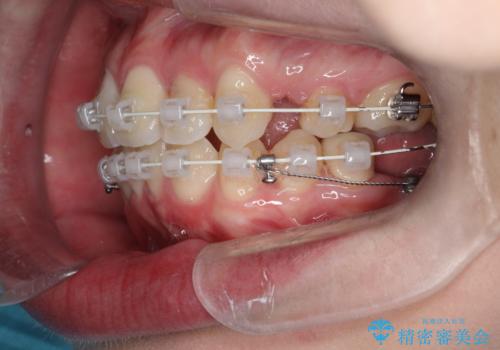

八重歯のワイヤーによる抜歯矯正 矯正治療と並行してセラミック治療も

- 八重歯と前歯のガタガタを主訴に来院されました。

左下の奥歯がすでに1本抜歯されており、ブリッジを装着されていました。

ブリッジを除去して、左下以外の上顎両側と右下の歯を合計3本抜歯して矯正する計画としました。

ブリッジを装着している歯は動かすことができないので、矯正前に除去する必要があることがあります。

今回の場合も、ブリッジを除去して矯正後にセラミックブリッジを装着しました。